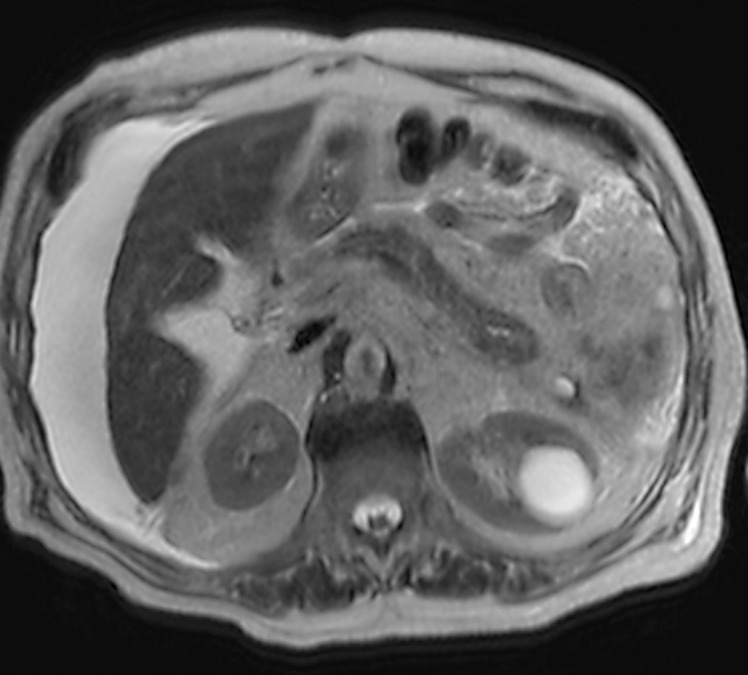

Case presentation: We present the case of a 79-year-old male with severe colitis resulting in perforation and pericolonic abscess formation adjacent to the pancreas, which resulted in an internal pancreatic fistula and pancreatic ascites. After 2 paracenteses, our patient ultimately underwent endoscopic retrograde cholangiopancreatography (ERCP) with sphincterotomy and pancreatic duct stent placement. The patient clinically improved and was ultimately discharged.

Conclusion: Follow-up ERCP was performed 2 months after discharge and showed no contrast extravasation, illustrating closure of the previous pancreatic fistula. Ultimately, our case demonstrates that cases of severe colitis may contribute to adjacent pancreatic fistula and ascites formation.